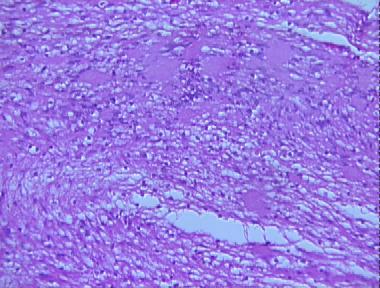

antoni B neurilemmoma

Histologic Features